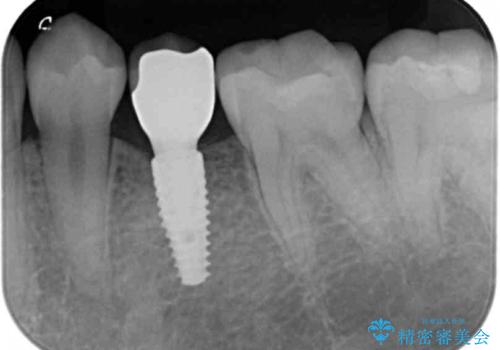

- 68.2万円 内訳: 部分矯正治療 22万円、インプラント 22万円、チタンカスタムアバットメント11万円、ジルコニアクラウン 11万円、矯正用シリンダーテック(仮歯) 2.2万円費用は治療当時の料金となります

矯正治療で歯を移動して得られたすき間はインプラントのクラウンで動かないようにできるためです。

保定が不要という点におきましては、部分矯正と補綴(被せ物)治療は非常に相性がよく、得られるメリットも大きいといえます。